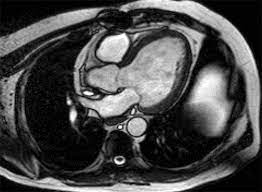

Cardiac MRI offers a detailed, clear view of the heart's structure and function, providing insights that traditional tests might miss. Unlike other tests, it doesn’t involve radiation, making it a safer option for repeated use. For someone like Ramesh, who needed clarity and confidence about his heart health, a Cardiac MRI was the answer.

Imagine the relief when Ramesh's cardiologist recommended a Cardiac MRI. The procedure was swift, and the results were comprehensive. The MRI scan provided a clear picture of his heart's condition, revealing that his symptoms were due to manageable issues rather than a severe cardiac event. With this knowledge, Ramesh could finally breathe easy, knowing that his heart was in safe hands.

1. Accuracy and Detail Cardiac MRI offers unmatched clarity, detailing every aspect of the heart's structure and function, which aids in accurate diagnosis.

3. Comprehensive Assessment It evaluates the heart's anatomy, function, and tissue characteristics in a single session, providing a holistic view of heart health.